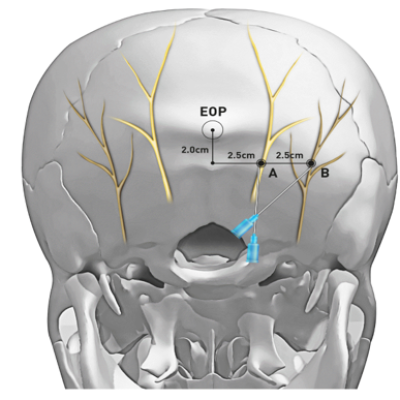

– Bloqueios anestésicos (como occipital e esfenopalatino) para diferentes tipos de dor aguda e crônica

FONTE: Occipital nerve block – The Nerve.